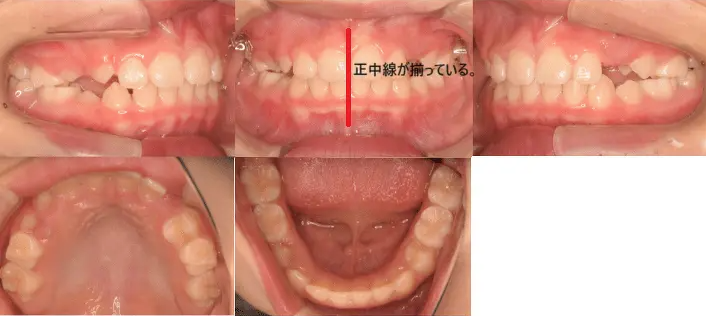

治療例③25歳7ヶ月

主訴 前歯がガタガタ。正中線もずれている。

治療内容 小臼歯4本を抜歯した後、マウスピース型カスタムメイド矯正歯科装置(製品名インビザライン 完成物薬機法対象外)を使用して主訴である叢生の改善を行った。

治療期間 2年

費用 80万円

【治療前】